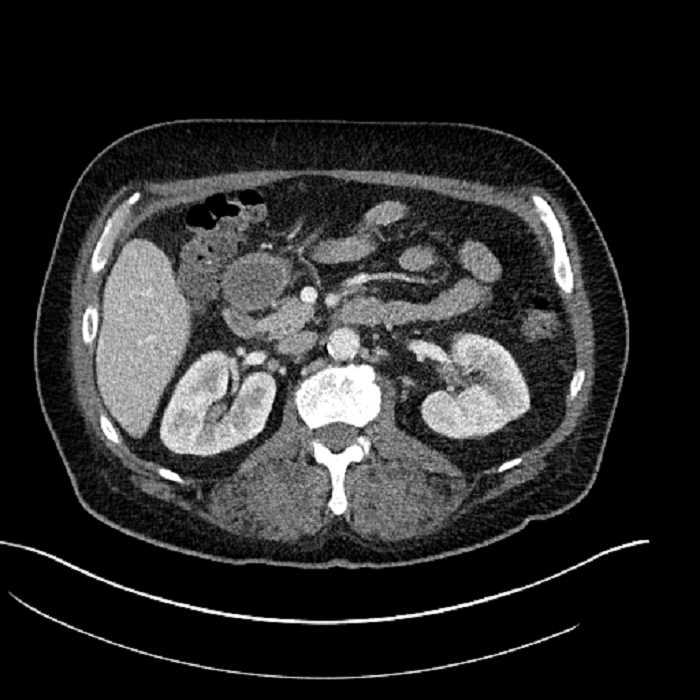

• Large fluid density structure in hepatic segments 7 and 8 measuring 10 x 7 x 7 cm with internal septation and circumferential ill-defined low density compatible with edema

• Peripherally enhancing subcapsular collections along the anterior margin of the left hepatic lobe measuring 3 x 1 cm and 2 x 1 cm

• Clearly marginated fluid density structure in segment 7 and several other scattered tiny hypodensities, which likely represent cysts

Acute sigmoid diverticulitis complicated by a small contained perforation and a large abscess in the right hepatic lobe. Additional small subcapsular abscesses along the anterior margin of the left hepatic lobe.

• The classic CT imaging appearance is a double target sign with internal low density surrounded by an internal enhancing rim (capsule) and a low density external rim (edema)

Hepatic abscess showing the double target sign with low density internally surrounded by a thin inner enhancing rim (red arrow) and ill-defined outer low density rim (yellow arrow). Blue arrow indicates an internal septation. Red arrows: additional smaller subcapsular abscesses. Red arrow: focal contained perforation associated with diverticulitis.